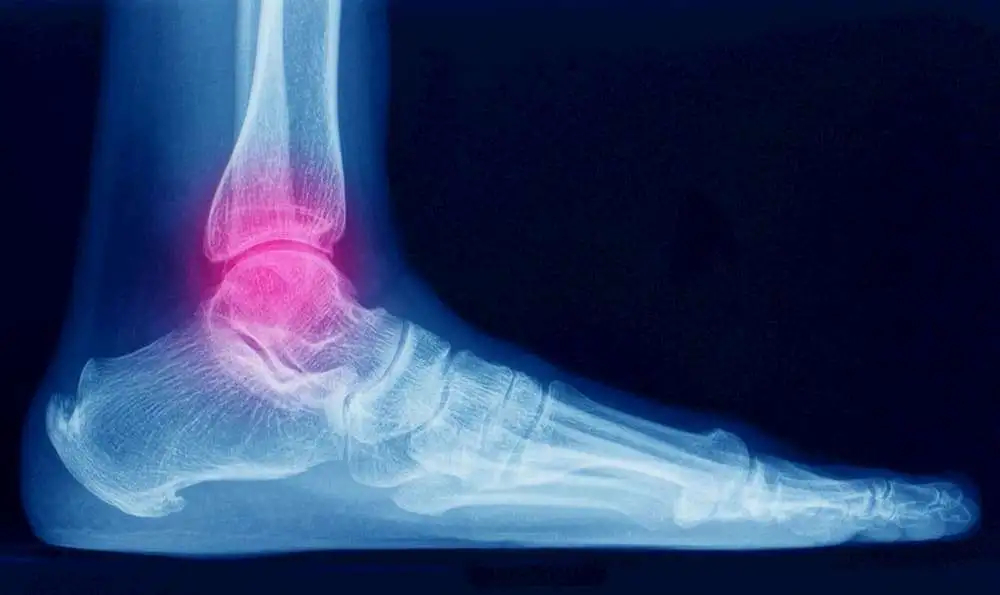

Factors concerned with pain intensity and physical limitations after lateral ankle sprains

Greater self-efficacy and younger age have been linked with fewer symptoms and shortcomings during recovery of an ankle sprain, but the extremity of the sprain is not.

In patients suffering from a lateral ankle sprain; swelling, tenderness, and ecchymosis don’t correlate with time to functional recovery. It has been known that psychosocial factors like symptoms of depression and low pain self-efficacy correlate with pain intensity and magnitude of limitations in patients with musculoskeletal problems.

The connection between pain self-efficacy or symptoms of depression along with ankle specific limitations and pain intensity in patients suffering from lateral ankle sprain were explored. Also, the correlation between estimation of sprain severity (grade) and (3) pain intensity or magnitude of ankle specific limitations has been discussed.

Three weeks after the surgery, a total of 84 patients with a lateral ankle sprain prospectively accomplished the Pain Self Efficacy Questionnaire, the Olerud Molander Ankle Score, Ordinal scale of Pain and the Patient Health Questionnaire-2 at enrollment and the Olerud Molander Ankle Score and the Ordinal scale of Pain. In the bivariable and multivariable analysis, the factors related to higher ankle specific limitations and symptoms were estimated.

When describing the confounding factors, greater self-efficacy (p = 0.01) and older age (p < 0.01) were significantly associated with greater ankle specific symptoms and limitations three weeks after the injury. This elucidated for 22% of the variability in ankle specific limitations and symptoms. No correlation was observed between the grade of the sprain and pain intensity or ankle specific limitations or symptoms.

It was thus concluded that the psychosocial factors (adaptiveness in response to pain in particular) elucidate more of the variation in symptoms and limitations after ankle sprain than the degree of pathophysiology. The influence of adaptive illness descriptions and recovery strategies as per the methods for improving self-efficacy (i.e. cognitive behavioral therapy) might intensify and speed recovery from ankle injuries and merit additonal examination.